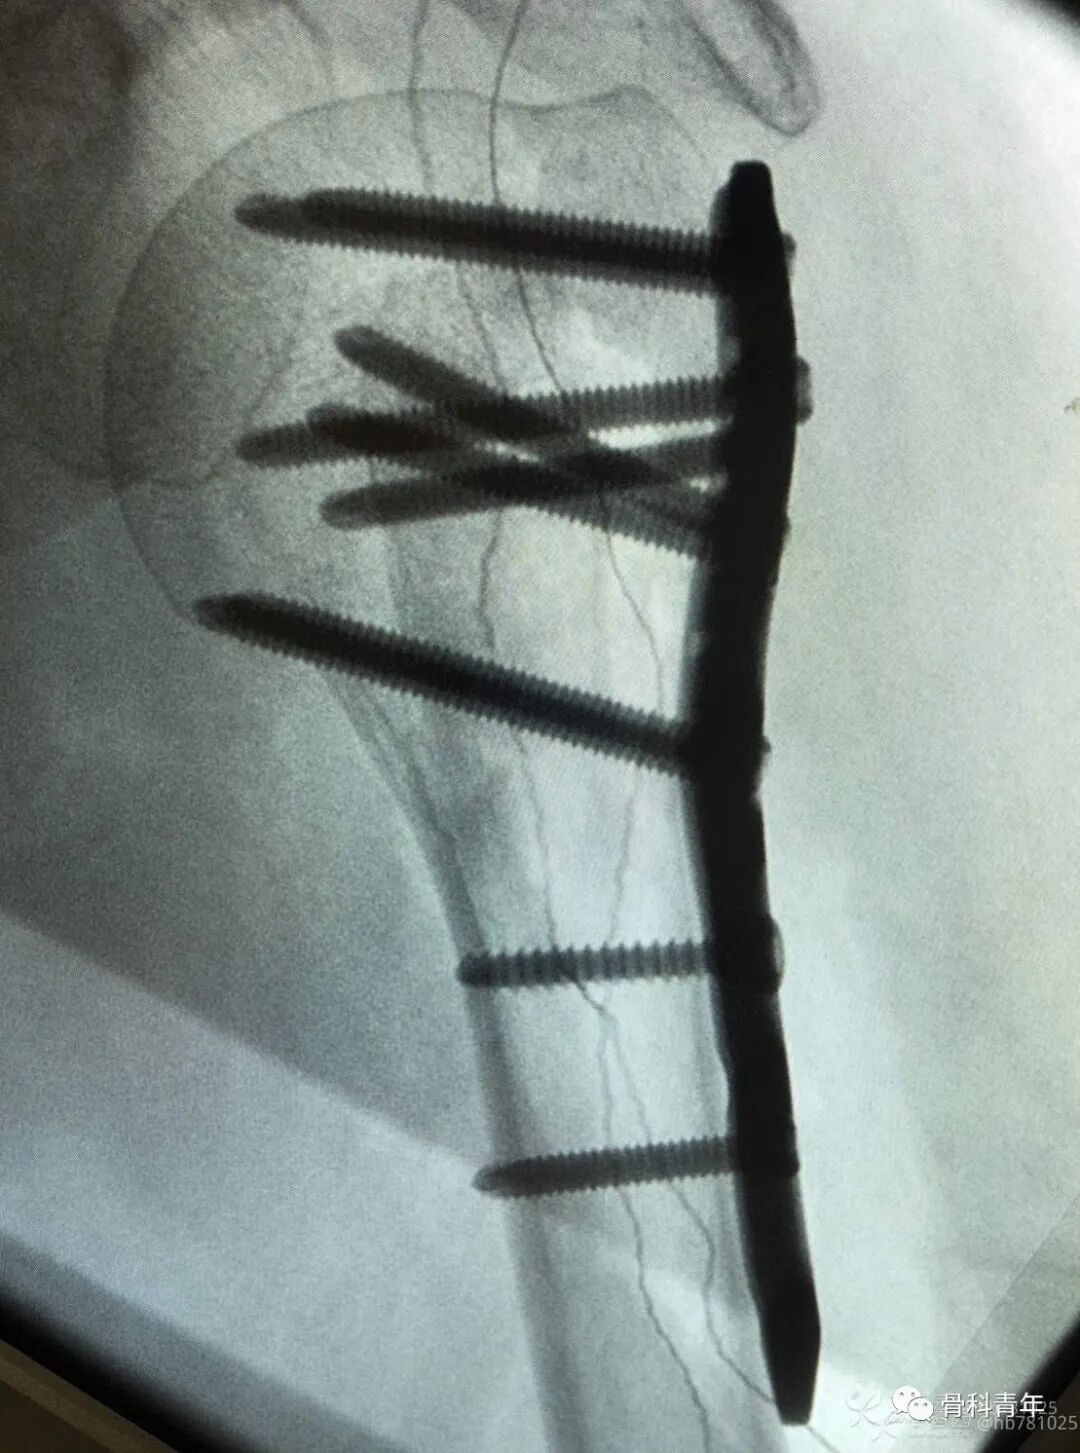

27.桡骨远端骨折